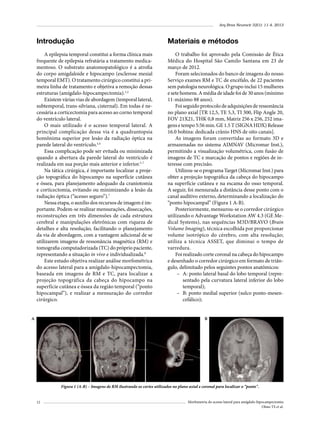

Figura 4 – Convexidade temporal basal tipo 1 (59%).

Figura 5 – Convexidade temporal basal tipo II (40%).

A profundidade da convexidade temporal basal é

variável. Foram identificados dois formatos (tipo I e II)

(Figuras 4 e 5). É relevante considerar essa classificação

no posicionamento cirúrgico da cabeça. No tipo II é

recomendada maior deflexão lateral para obter melhor

ângulo de acesso (Figuras 4 e 5).